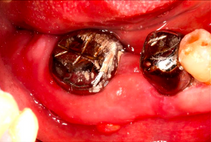

- Surgical removal of excessive gum tissues and extraction of multiple poor prognosis teeth were carried out as well

- She was kept under strict follow up and advised to comply with meticulous oral hygiene measures throughout treatment

Review in 2 years